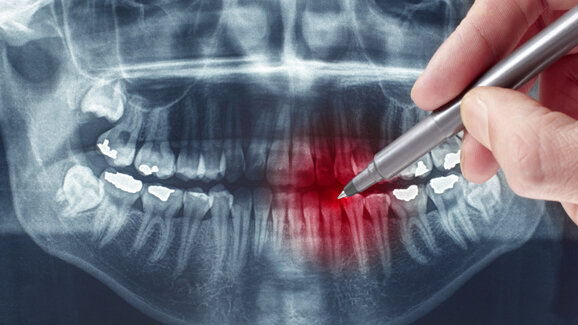

Forscher der University of Maryland/Dental School fanden es in Studien heraus: Männer haben ein deutlich höheres Risiko, an Parodontitis zu erkranken als Frauen. Ursache dafür bilden anscheinend männliche Sexualhormone, die sich auf das Immunsystem und damit auch auf die körpereigene Regulierung von Entzündungen auswirken. Des Weiteren untersuchten die Experten, ob eventuell auch genetische Faktoren in das Risiko für die gefährliche Entzündung des Zahnhalteapparates mit hineinspielen. „Auch wir beobachten in unserer Praxis, dass Männer häufiger und schwerer an Parodontitis leiden als Frauen“, sagt Dr. Uwe Hildebrand, MSc, Spezialist für Parodontologie und leitender Zahnarzt an der Zahnklinik Rhein-Ruhr, und fügt hinzu: „Daher sollte das männliche Geschlecht auch regelmäßig zur Kontrolluntersuchung kommen. Hier können wir die Tiefe der Zahntaschen messen und bereits erste Anzeichen einer Parodontitis erkennen und gegebenenfalls behandeln.“

Vereinfacht besagt die Studie aus den USA, dass Verlauf und Ausheilungsgeschehen einer Parodontitis mit der angeborenen Immunreaktion zusammenhängen, welche sich bei Männern und Frauen aufgrund unterschiedlicher Konzentrationen von Sexualhormonen deutlich unterscheidet. So weisen Frauen eine höhere Anzahl von Antikörpern auf und daher auch eine verstärkte Abwehrkraft gegen Keime aller Art, wie die Parodontitis verursachenden Bakterien. Diese nisten sich bei einer Erkrankung beispielsweise im Zahnfleischbett oder Kieferknochen ein und rufen dort entzündliche Veränderungen hervor. „Damit beginnt ein schleichender, häufig zunächst schmerzloser und daher unbemerkter Prozess. Er zieht in der Regel Zahnfleisch- und Kieferknochenschwund nach sich und kann so für den Verlust einzelner oder sogar mehrerer Zähne sorgen“, erklärt Dr. Hildebrand den Krankheitsverlauf.